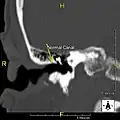

Exostoses in the ear canal, as seen through otoscopy

Surfer's ear is the common name for an exostosis or abnormal bone growth within the ear canal. They are otherwise benign hyperplasias (growths) of the tympanic bone thought to be caused by frequent cold-water exposure.[1] Cases are often asymptomatic.[1] Surfer's ear is not the same as swimmer's ear, although infection can result as a side effect.

Irritation from cold wind and water exposure causes the bone surrounding the ear canal to develop lumps of new bony growth which constrict the ear canal. Where the ear canal is actually blocked by this condition, water and wax can become trapped and give rise to infection. The condition is so named due to its high prevalence among cold water surfers, although it can occur in any water temperature due to the evaporative cooling caused by wind and the presence of water in the ear canal.

The normal ear canal is approximately 7 mm in diameter and has a volume of approximately 0.8 ml (approximately one-sixth of a teaspoon).[5] As the condition progresses, the diameter narrows and can even close completely if untreated, although people generally seek help once the passage has constricted to 0.5–2 mm due to the noticeable hearing impairment. While not necessarily harmful in and of itself, constriction of the ear canal from these growths can trap debris, leading to painful and difficult to treat infections.